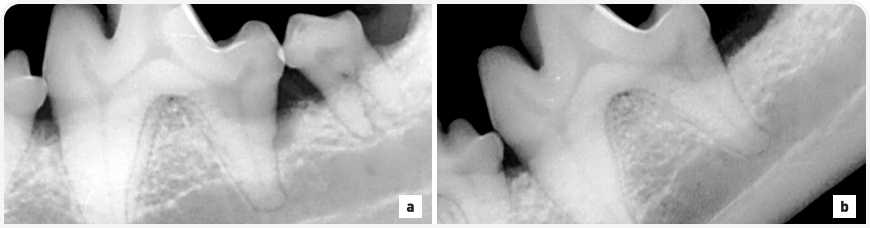

Рисунок 4. (a) Внутриротовая рентгенограмма зубов (визуализация левых моляров нижней челюсти, параллельная техника) у норвич-терьера демонстрирует тяжелый пародонтит на дистальном корне первого левого моляра нижней челюсти (20%-ная горизонтальная потеря кости плюс 30%-ная вертикальная потеря кости). Лечение включало в себя удаление второго левого моляра нижней челюсти и направленную регенерацию ткани дистального корня первого левого моляра нижней челюсти. (b) Внутриротовая рентгенограмма зубов (тот же метод), полученная через три месяца при послеоперационном обследовании того же пациента; степень пародонтита улучшилась с 50%-ной потери кости до ~20-30%-ной потери кости, произошло ремоделирование лунки второго левого моляра нижней челюсти.